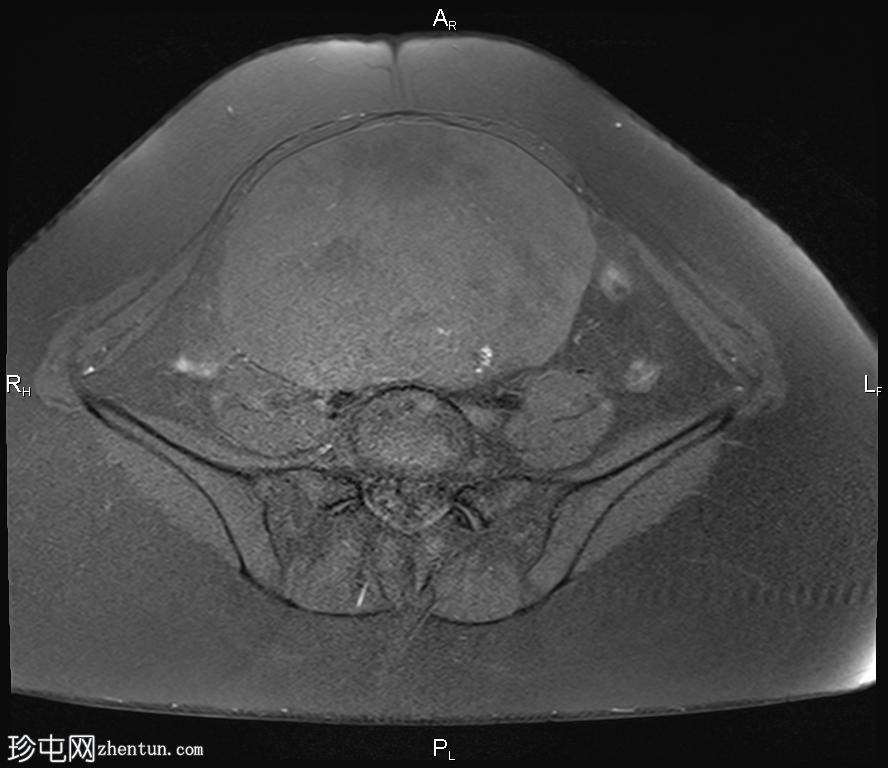

轴向位

T2

盆腔内可见一巨大多分叶实性肿块,内部有隔膜,T2WI信号不均匀,T1WI信号不均匀,呈低信号。肿块内散在分布囊性/坏死性病变。

肿块外可见子宫和右侧卵巢,肿块似源自左侧卵巢。该肿块压迫膀胱和两侧远端输尿管,并导致肠管和血管结构移位,但无侵袭或包裹征象。

造影后,肿块呈不均匀强化,隔膜强化。

远端髂腹旁和两侧髂骨旁区域可见少量肿大淋巴结。